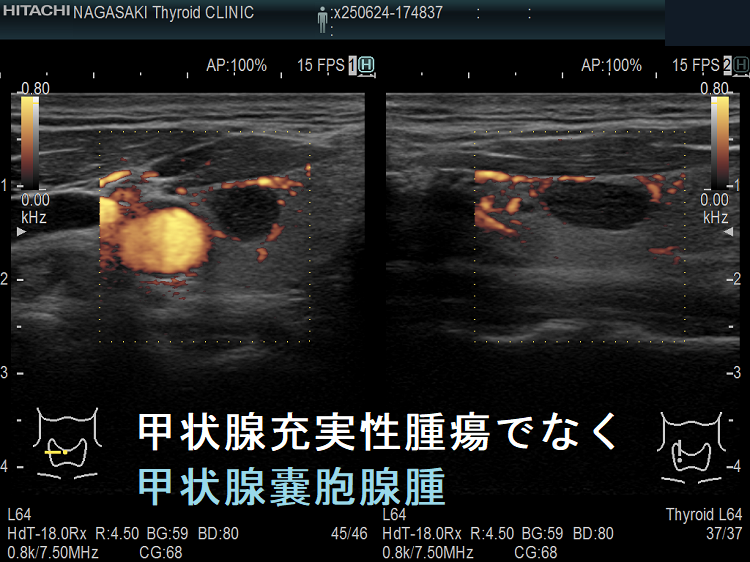

甲状腺のう胞に見えるが実は甲状腺腫瘍

甲状腺のう胞(甲状腺嚢胞)に見えるが甲状腺腫瘍 超音波(エコー)画像;低エコー(真っ黒)で、内部にコロイド様物質があるように見えるため、甲状腺のう胞(甲状腺嚢胞)と間違えます。

甲状腺のう胞に見えるが実は甲状腺腫瘍 eFlow

甲状腺のう胞(甲状腺嚢胞)でなく甲状腺腫瘍  eFlow(イー フロー);内部血流が、はっきり見えて甲状腺腫瘍なのがわかります。

2. 充実性腫瘍に見えても、高感度パワードプラーで低流速の細い血管が検出されず、実はただの甲状腺のう胞腺腫(甲状腺嚢胞腺腫)(内部の不均質な実質様エコーは粘稠なコロイド物質)

だったなど、臨床診断が覆る場合があります。特に1.の場合は、甲状腺腫瘍甲状腺のう胞(甲状腺嚢胞)と間違えると大変な事になります。極めて低エコーな甲状腺腫瘍は、甲状腺乳頭癌甲状腺濾胞癌甲状腺髄様癌甲状腺悪性リンパ腫の可能性があるからです。

1. ケース①-④ 甲状腺のう胞(甲状腺嚢胞)に見えるが甲状腺腫瘤(結節)・甲状腺腫瘍

2. ケース⑤-⑥ 甲状腺充実性腫瘍でなく甲状腺のう胞腺腫(甲状腺嚢胞腺腫)

ケース⑤ 甲状腺充実性腫瘍でなく甲状腺のう胞腺腫(甲状腺嚢胞腺腫)

充実性腫瘍に見えるが、のう胞腺腫

通常Bモードでは、充実性腫瘍に見える。

高感度パワードプラーで低流速の細い血管が検出されず、甲状腺のう胞腺腫(甲状腺嚢胞腺腫)(内部の不均質な実質様エコーは粘稠なコロイド物質)

ケース⑥ 甲状腺充実性腫瘍でなく甲状腺のう胞腺腫(甲状腺嚢胞腺腫)

甲状腺充実性腫瘍でなく甲状腺のう胞腺腫(甲状腺嚢胞腺腫)1

甲状腺充実性腫瘍でなく甲状腺のう胞腺腫(甲状腺嚢胞腺腫);内部エコーが存在し、あたかも甲状腺充実性腫瘍に見える

甲状腺充実性腫瘍でなく甲状腺のう胞腺腫(甲状腺嚢胞腺腫)[拡大]

甲状腺充実性腫瘍でなく甲状腺のう胞腺腫(甲状腺嚢胞腺腫)[拡大];拡大しても、やはり甲状腺充実性腫瘍に見える

甲状腺充実性腫瘍でなく甲状腺のう胞腺腫(甲状腺嚢胞腺腫)ドプラーモード

甲状腺充実性腫瘍でなく甲状腺のう胞腺腫(甲状腺嚢胞腺腫)ドプラーモード;内部に血流が存在せず、生きた組織ではない。内部は粘稠な液体。

甲状腺充実性腫瘍でなく甲状腺のう胞腺腫(甲状腺嚢胞腺腫)[拡大]ドプラーモード

甲状腺充実性腫瘍でなく甲状腺のう胞腺腫(甲状腺嚢胞腺腫)[拡大];拡大しても、やはり内部に血流が存在せず、生きた組織ではない。内部は粘稠な液体。